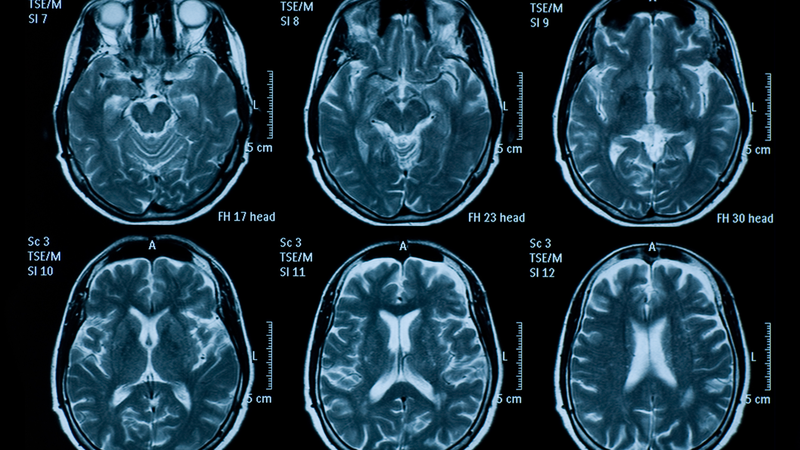

Các nhà khoa học tại Trung tâm Y khoa đại diện bởi Edwardson và các đồng nghiệp đã phát hiện ra rằng việc kết hợp kỹ thuật MRI truyền thống với một phương pháp mới gọi là hình thái dựa trên khuếch tán tensor (DTBM) có thể cung cấp hình ảnh chi tiết hơn về các đường dẫn chất trắng đến chi. Kỹ thuật này giúp xác định liệu các cáp này có bị suy teo hay không, một thông tin quý giá để đánh giá khả năng hồi phục sau đột quỵ của bệnh nhân.

DTBM là một kỹ thuật tiên tiến kết hợp thông tin định hướng với hình dạng và kích thước của các cấu trúc não được hình ảnh hóa. Trước đây, các nhà thần kinh học thường gặp khó khăn trong việc phân biệt các cáp chất trắng từ chất xám bằng cách sử dụng các phương pháp hình thái thông thường. Tuy nhiên, với sự ra đời của DTBM, các nhà nghiên cứu có thể lập bản đồ và định lượng các thay đổi theo thời gian trong các đường dẫn chất trắng.

Trong nghiên cứu của Edwardson và các đồng nghiệp, họ đã sử dụng DTBM để đo lường sự suy teo của đường dẫn corticospinal - đường dẫn chính từ não xuống tủy sống giúp điều khiển các động tác tay và chân. "Tới mức chúng tôi biết, đây là nghiên cứu đầu tiên cho phép chúng tôi đo được sự suy teo của các đường dẫn này trong những người sống sót sau đột quỵ", Edwardson chia sẻ.